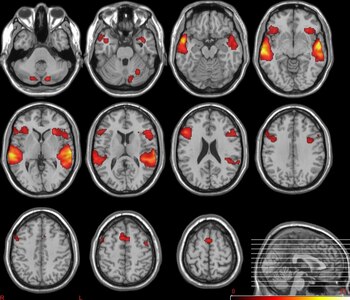

Los investigadores utilizaron la resonancia magnética para comparar la estructura de la materia blanca y el umbral de conciencia de adultos sanos, pacientes con trastorno bipolar con y sin síntomas psicóticos y pacientes con esquizofrenia.

El umbral de conciencia corresponde a cuánto tiempo se debe presentar un estímulo visual en una pantalla para que se transmita a través del cerebro y se vuelva consciente; cuanto más corto sea, mejor será el acceso consciente. Los umbrales aumentaron significativamente en los pacientes con psicosis en comparación con los que no la padecían.

En todos los participantes, los umbrales más bajos se correlacionaron con una mayor conectividad de materia blanca en áreas de larga distancia. Estos resultados significan que la conectividad alterada de la materia blanca no induce psicosis directamente, pero puede hacerlo a través de su efecto sobre el umbral de conciencia.